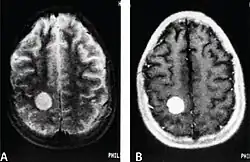

MRI of a cardiac angiosarcoma that has metastasised to the brain.

Primary cardiac angiosarcoma is an angiosarcoma that arises in the heart. Despite being very rare they are the most common malignant primary heart tumor with 10–25%[12][3] of cases being angiosarcomas. Symptoms may include shortness of breath, chest pain (46%[12]), hypotension and syncope. Superior vena cava syndrome is reportedly a complication of cardiac angiosarcoma.[7] Due to the non-specificity of symptoms and rarity of the disease it is often missed by doctors and initial diagnosis may be delayed. A 2012 study reported that 56% of patients presented with pericardial effusion with or without cardiac tamponade.[12] The most common finding on imaging is cardiomegaly. Prognosis is generally very poor with a mean survival rate of three months to four years following diagnosis.[7] Metastasis at time of diagnosis is common.[12]